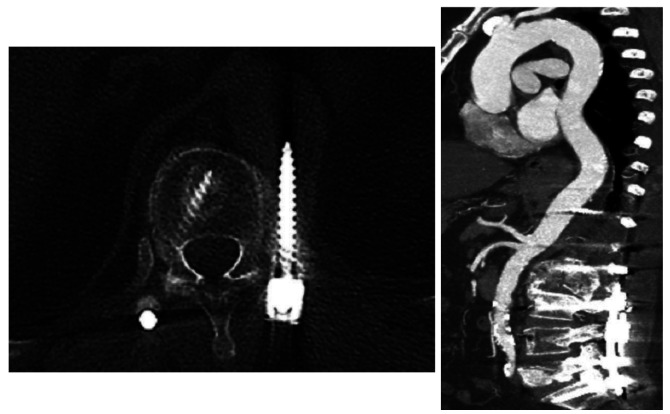

Stabilization of spine using transpedicular screws is the most commonly used instrumentation technique among spinal surgeons. The 'free hand' technique is considered relatively safe and can be performed under x-ray control. Vascular injuries with misplaced screws are rare but potentially fatal complications. Injury of thoracoabdominal aorta by malpositioned screw demands a multidisciplinary approach. Injury of vessel wall might demand screw removal and vessel wall repair. Here we present a case of 72-year-old female patient who underwent long segment fixation of thoracolumbar spine. During follow up, computed tomography (CT) scan and afterwards aortography showed a lesion of the posterior aortic wall by malpositioned screw without signs of bleeding. After meticulous preparation, combined endovascular repair with stent-graft and removal of the penetrating screw were performed. Endovascular treatment was performed simultaneously with screw removal. During screw removal, the patient was in lateral decubital position. The patient was discharged on postoperative day 8. Follow up CT aortography 6 months later showed no leak or other changes in the aorta. We found combined endovascular vessel repair with simultaneous screw removal safe and sufficient for this kind of aortic injury. Although lateral decubital position bears limitations, it gives enough space for the operator. Performing intraoperative aortography provides good insight into stent position and possible bleeding after screw removal.

Abstract Image